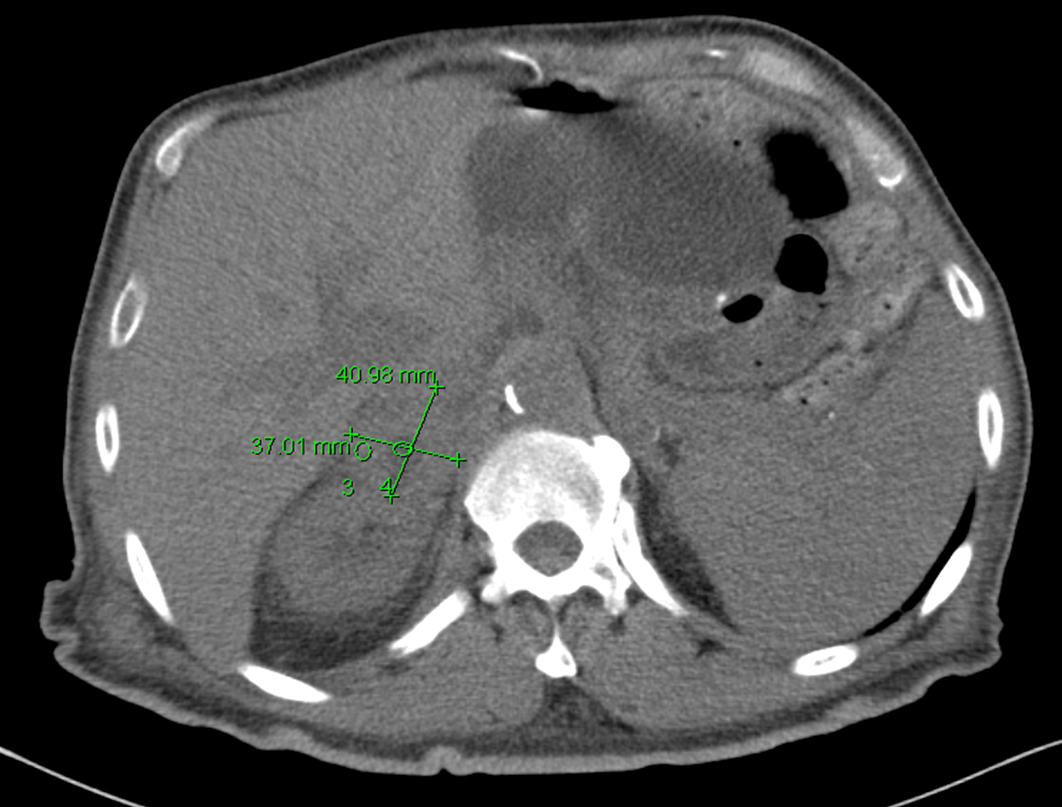

The CT scan revealed a 5 x 2.2 cm mass lesion in the right renal/suprarenal region inseparable from the kidney and the right adrenal gland and the differential diagnosis was either a RCC or adrenal carcinoma. He then proceeded to an MRI abdomen.

This again showed a mass in the right suprarenal region, inseparable from the right kidney and adrenal gland with some central necrosis. At this point, the decision was made to proceed with a partial nephrectomy for likely carcinoma.